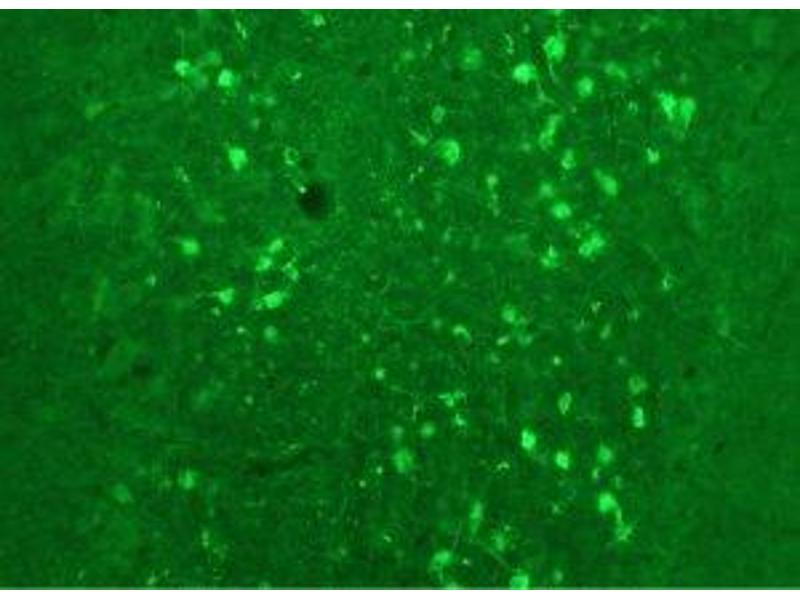

This 绵羊 多克隆 antibody specifically detects Calretinin in WB, IHC 和 ELISA. It exhibits reactivity toward 豚鼠.

Western Blotting (WB), Immunohistochemistry (IHC), ELISA

Specific for endogenous levels of the ~29 kDa calretinin protein in Western blots of rat brain lysate. The antibody also works well for immunohistochemistry on formalin or paraformaldehyde perfused rat brain tissue sections.

Our Anti-Calretinin Antibody primary antibody is sheep polyclonal. It detects rat Calretinin and is protein g purified. It is great for use in ELISA, WB, IHC.